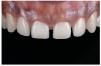

Figs. 31a y 31b. Las carillas laminadas cerámicas de disilicato de litio (e.max Press/e.max Ceram, Ivoclar Vivadent) sobre el modelo maestro. Las pequeñas carillas parciales en los caninos superiores se cuecen sobre un modelo pirorresistente (e.max Ceram).

Fig. 33. Las cuatro carillas laminadas de los dientes anteriores realizadas en disilicato de litio se colocaron con una pasta de prueba en boca de gran claridad. Éste fue también el color de pasta finalmente seleccionado.